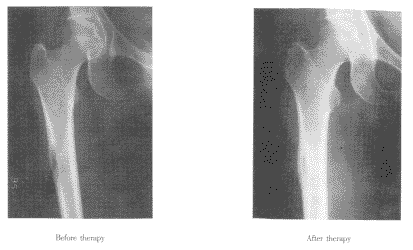

图2 女性,45岁,小细胞肺癌。治疗前X线检查发现右股骨中段有“溶骨型”骨破坏,皮质变薄。接受4次153Sm-EDTMP治疗,总剂量大于7400MBq。5个月后再次照X线片,股骨病灶已成“硬化型”,骨皮质变厚,有明显骨修复。

Fig 2 This is a 45-year-old female patient with small cell lung cancer. X-ray shew that there was a lytic disease in right femur with bone cortex becoming thinner. She received 7400MBq153 Sm-EDTMP. Five months later, X-ray showed that there was significant bone repairing.

2.3 整体治疗效果 110例患者中有12例获CR,病灶消失(图1),Karnofsky评分上升20分左右,止痛药用量减少一半或停用。20例患者获PR,转移灶数量减少,病灶缩小;X线检查示溶骨性病灶转变为硬化型,可见骨修复(图2);Karnofsky评分上升10~15分。153 Sm-EDTMP治疗肺癌骨转移灶的总有效率(CR+PR)为29.1%(32/110)。病变较小(<2cm)且位于胸、腰椎体和肋骨者,其转移灶消失的例数明显多于病变范围较大(>2cm,呈不规则巨块状)及位于骨盆和长骨者(P<0.05)。